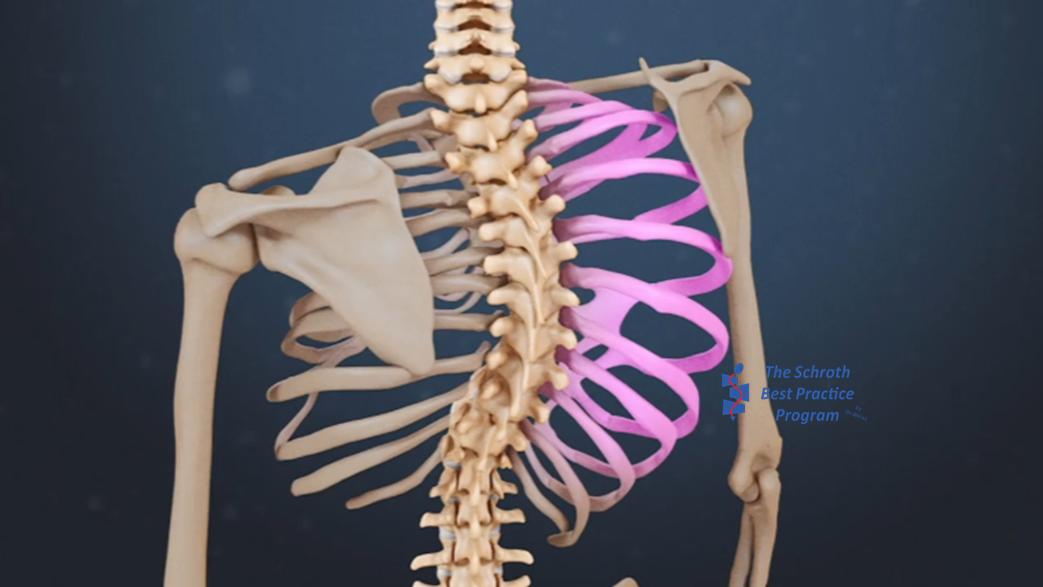

Kouwenhoven等人于2006年发现,即使是没有脊柱侧凸的普通人,在胸椎的第6~8节段有右旋的趋势,右旋角度最大位2°。

从解剖学意义上,筋膜和膈肌的张力是不对称的,因此肌肉骨骼运动系统会有一定的正常运动偏差。

早在1984年Dickson就给出了一种可能的解释,在第5到第8胸椎椎体的向右旋转与在该位置的降主动脉及其和心脏的搏动相关。

Kouwenhoven等人(2007)在研究中对37名没有脊柱侧凸但是存在内脏异位的受试者进行了横切面的磁共振检查。内脏异位是一种罕见的、但不属于疾病的现象,即器官在体内另一侧镜面反转。研究发现这些受试者的椎体旋转方向与无脊柱侧凸且器官位置正常的人相反。

所以为什么胸椎侧凸经常发生在右侧,为什么胸椎更容易顺时针旋转?可能和我们的身体内部构造息息相关!